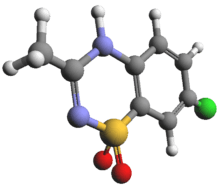

- Chlorothiazide[2]

- Diazoxide [7]